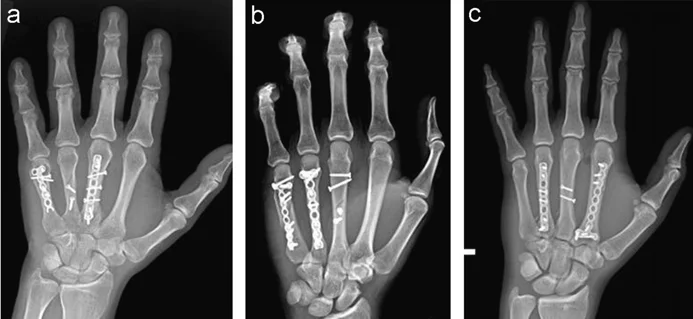

- Displaced / Rotated / Multiple

- Treated by internal fixation (screws / plates / wires)